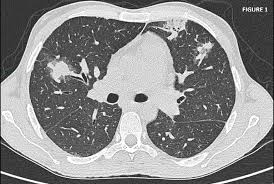

Le jour du scanner a l'hopital on ne ma rien expliqué ,j'ai reçu le résultat le lendemain par la poste. Ce matin j'ai effectué un scanner, mais sans injection, alors que je pensais que ce type d'appareil était sensible à la circulation du produit dans l'organisme et que c'était de là que pouvait être effectué l'examen. Acquisition hélicoïdale millimétrique sans injection sur le thorax. Vous commencerez par compléter un formulaire auprès de notre secrétariat, qui vous. Dans de nombreux cas, le scanner thoracique requiert l'injection préalable d'un produit de contraste afin d'améliorer la lisibilité des images et de détecter plus aisément une anomalie. Indications, préparation et déroulement de la procédure. Hospitalisation pour un asthme négligé. Un scanner permet de reconstituer des parties de corps en 3d.

Dans de nombreux cas, le scanner thoracique requiert l'injection préalable d'un produit de contraste afin d'améliorer la lisibilité des images et de détecter plus aisément une anomalie.

Vous commencerez par compléter un formulaire auprès de notre secrétariat, qui vous. Hospitalisation pour un asthme négligé. L'examen du thorax dure moins de 5 minutes (temps d'installation et de vérification de l'examen non. Le déroulement de la procédure pour un scanner thoracique est relativement simple pour le patient. Le scanner thoracique permet d'examiner sur des coupes transversales fines les poumons, leur enveloppe appelée plèvre, et les vaisseaux qui irriguent les bronches et les poumons. The sql injection scanner (light scan) performs a quick and fast scan of a target url that allows it to identify vulnerabilities in web applications. Dans de nombreux cas, le scanner thoracique requiert l'injection préalable d'un produit de contraste afin d'améliorer la lisibilité des images et de détecter plus aisément une anomalie. Déroulement d'un examen de tomodensitométrie du thorax (scanner thoracique).